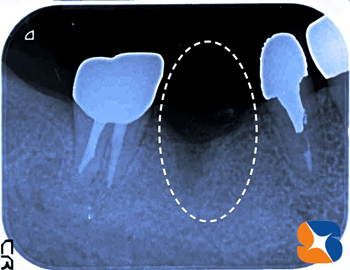

歯肉の手術から1ヶ月後。見事に盤石の歯肉が完成。これなら、如何なる歯ブラシ圧、力に耐えることが出来ます。つまり、一生涯インプラント生活を保証できるのではないでしょうか。

最後は、型取り。その後、Dr自身が患者様のお口の中の状態を吟味しながら、最適の形のセラミック歯をセレックを使って完成させます。

治療期間約6ヶ月

総費用37万(税別)